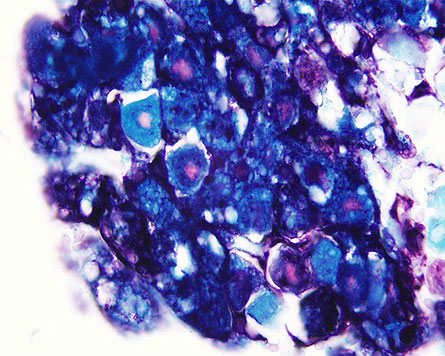

Infection with the herpes simplex virus usually triggers an acute phase that may be accompanied by a fever and cold sores. Then the symptoms subside, but the virus retreats and hides in the trigeminal ganglia, a cluster of nerve cells near each ear in people. Once ensconced in nerve cells, the virus never goes away. “If I can borrow a line from the diamond people, herpes is forever,” says Steven Triezenberg, a researcher at the Van Andel Institute in Grand Rapids, Mich.

In the new study, mice were infected with herpes virus carrying a mutated, inactive form of VP16. After the initial infection had faded, the researchers stressed the mice by raising body temperature and watched to see how many mice had a recurrence of a viral outbreak. The researchers used a new technique to monitor viral gene activity and viral proteins in individual nerve cells. Stress did not reactivate the virus in these mice.